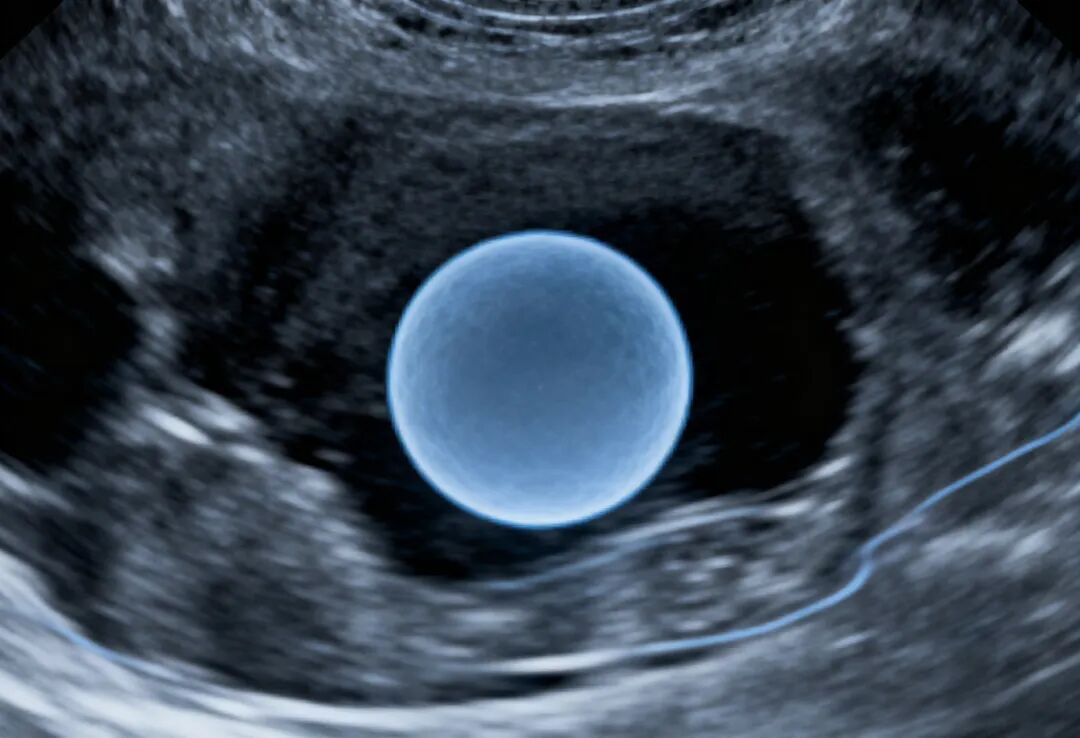

第三代试管婴儿:试管婴儿移植后多久可以测血HCG?